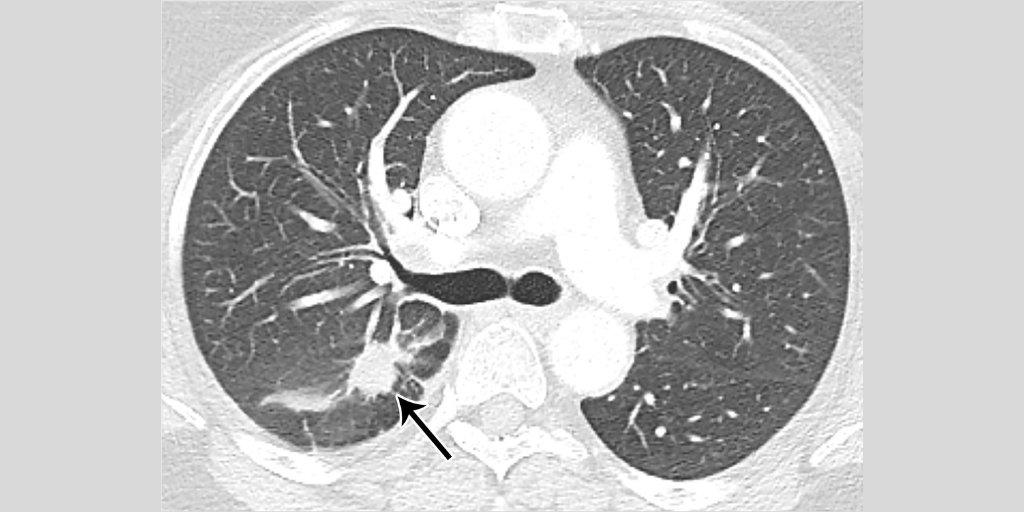

Imágenes de

#CT de un caso de neumonía con PCR positivo para#2019nCoV Reconstrucción 3D VR muestra la distribución de las opacidades del vidrio esmerilado Hallazgos bastante inespecíficos!#radiology#coronavirus@radiology_rsna#radiología#ChestRad https://pubs.rsna.org/doi/10.1148/radiol.2020200257 …pic.twitter.com/Xrg6RU3Lhr -